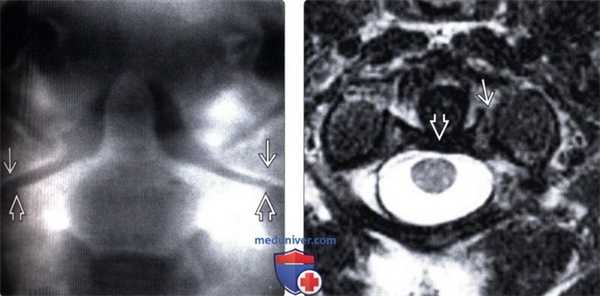

(Слева) На фронтальной томограмме, полученной через зубовидный отросток, отмечается латеральное смещение боковых масс С1 относительно боковых масс С2.

(Справа) На аксиальном Т2-ВИ пациента со взрывным переломов С1 видна интактная поперечная связка атланта. Обратите внимание на отрывной перелом костного фрагмента в области прикрепления этой связки при сохранении целостности самой связки.